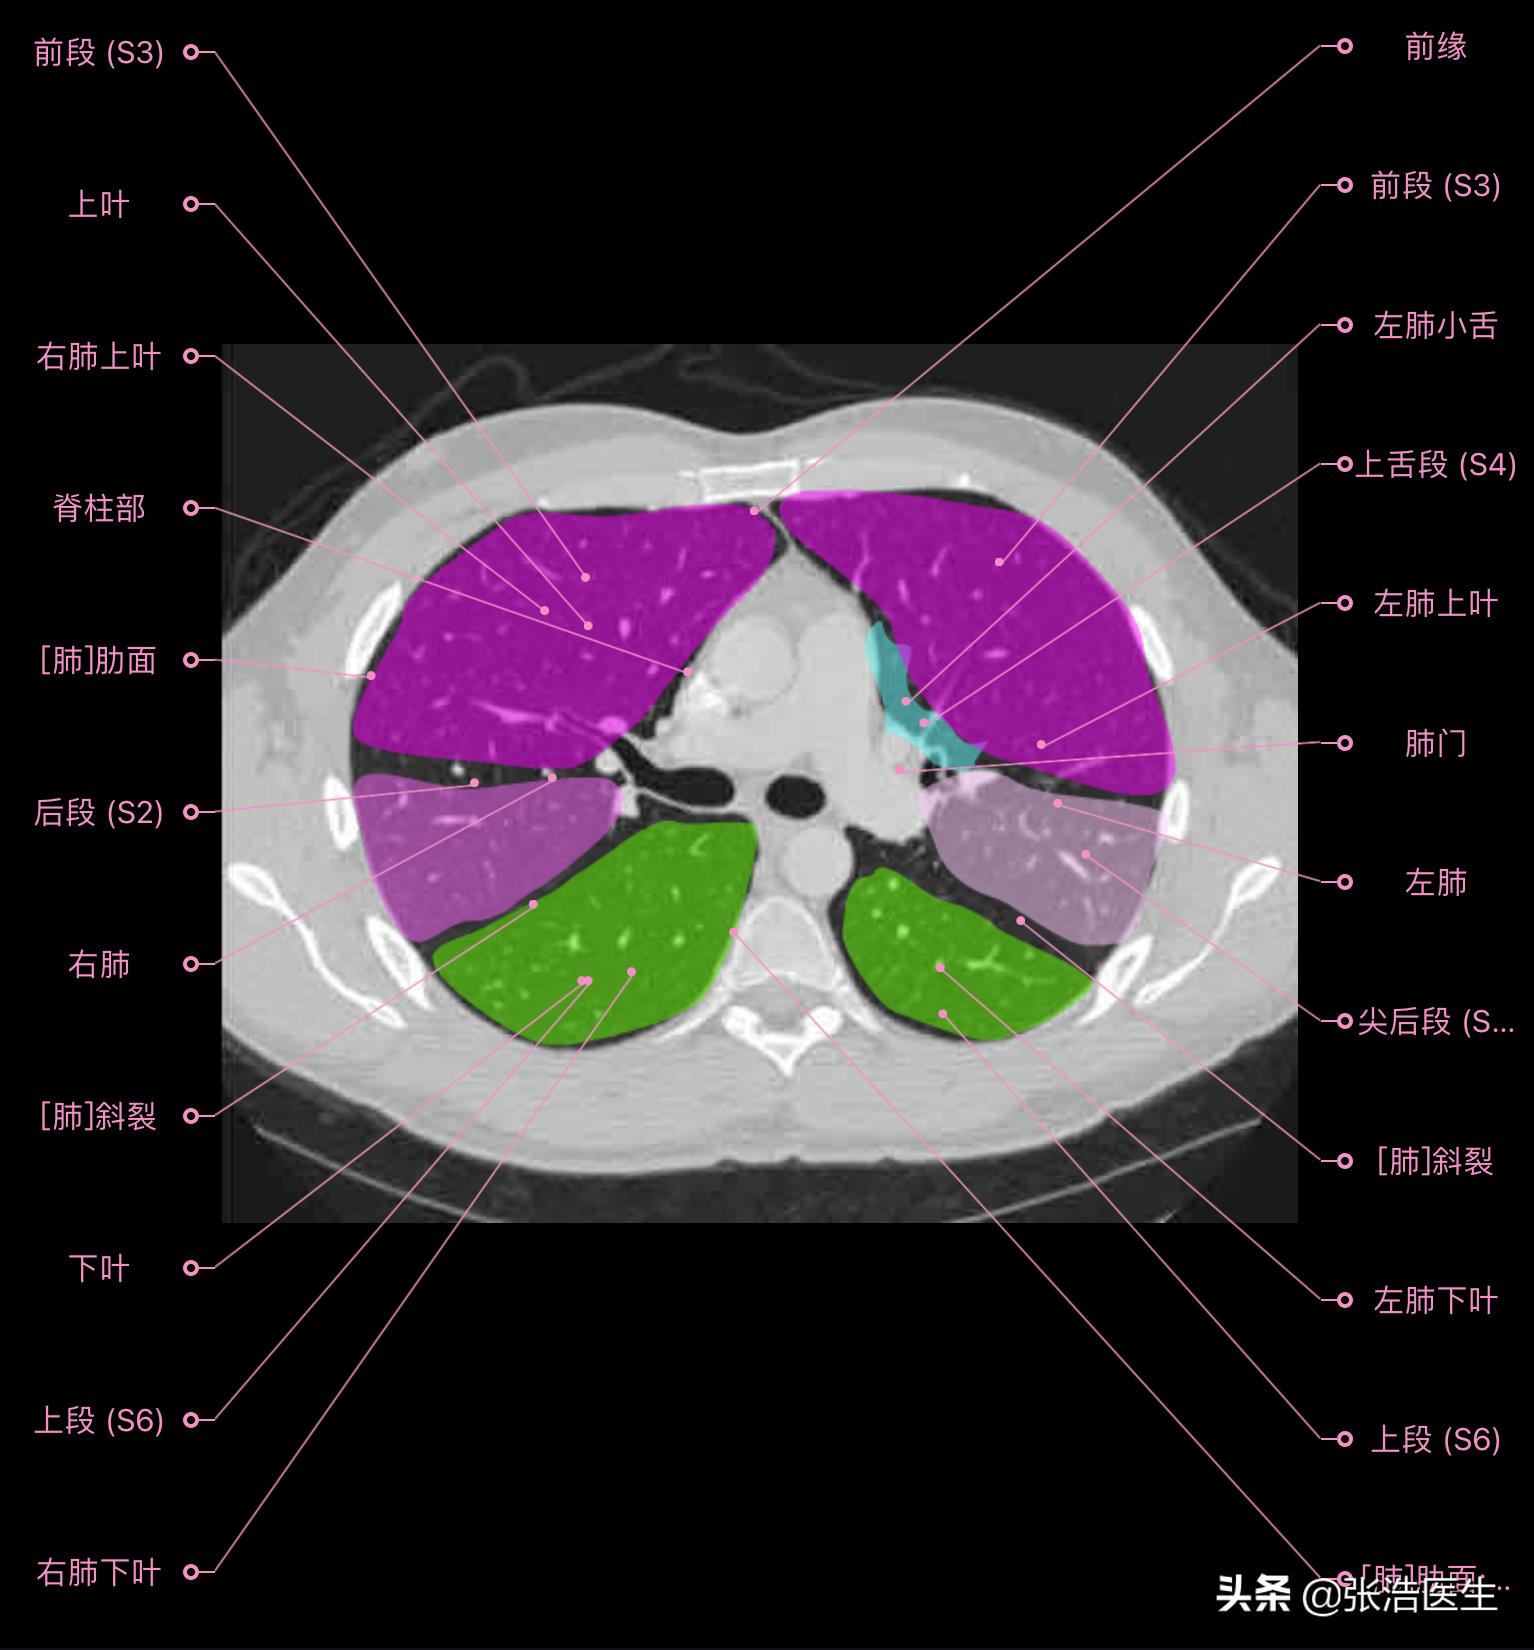

肺部CT横断面高清解剖图谱(图层1)